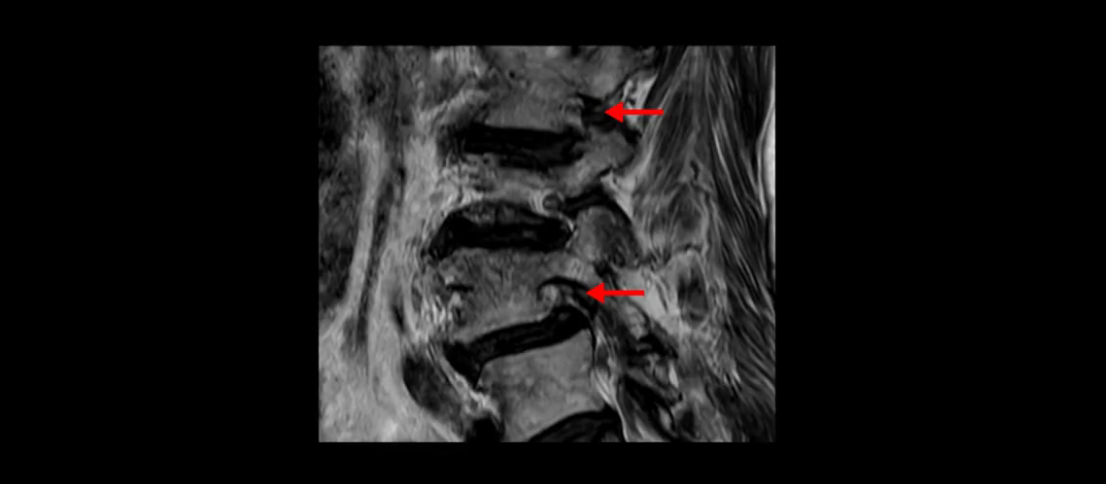

먼저 이분 MRI를 보고 자세히 설명해 드린 후 어떻게 허리 여러 마디에서 협착과 전방전위로 신경이 심하게 눌려 보이는 환자가 수술 없이 좋아질 수 있는지, 또 치료는 어떻게 하는지 설명해 드리겠습니다.

이분 MRI 보시면 허리 3마디의 퇴행이 매우 심합니다.

4번 5번에는 뼈가 밀려 나간 전방전위증도 있고,

또 척추관협착도 매우 심합니다.

척추관이 심하게 좁아져 있습니다.

이렇게 여러 마디가 안 좋고 뼈도 밀려 나가 있으니까 나사박는 수술해야 하는데, 대학병원에서도 수술을 한 번에 못 하고 두 번에 나눠서 해야 한다고 들으셨습니다. 왼쪽으로 신경가지가 빠져나가는 추간공도 많이 좁아져 있습니다.

이렇게 신경 구멍들이 좁아져 있고 신경이 눌리니까 엉덩이와 다리가 너무 저리고 아파서 아예 일어서질 못하니까 휠체어를 타고 병원에 내원하셨는데요. 그럼 어떻게 이분처럼 신경이 눌려있는 환자분들을 수술 없이 치료해서 잘 걷게 만들고 엉덩이와 다리가 저리고 아픈 증상이 사라지게 할까요? 지금부터 설명해 드립니다.